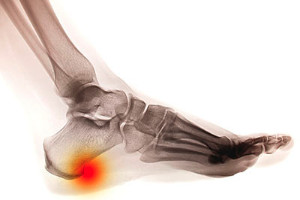

Plantar fasciitis causes heel pain that often makes the first steps in the morning feel sharp and uncomfortable. This condition occurs when the thick band of tissue along the bottom of the foot becomes inflamed or torn. The heel may feel tender, tight, or even slightly swollen, and pain can return after long periods of standing or walking. Contributing factors include overuse, wearing unsupportive shoes, or having flat feet or high arches that place added stress on the tissue. A podiatrist begins with a careful evaluation of symptoms and foot structure and orders imaging if needed. Treatment focuses on reducing pain and improving support through custom orthotics, footwear changes, and targeted exercises to improve flexibility and strength. Early care can help prevent the condition from becoming long-lasting. If you are dealing with painful plantar fasciitis, it is suggested that you make an appointment with a podiatrist.

Plantar fasciitis is a common foot condition that is often caused by a strain injury. If you are experiencing heel pain or symptoms of plantar fasciitis, contact one of our podiatrists from Active Foot and Ankle Care, LLC. Our doctors can provide the care you need to keep you pain-free and on your feet.

Plantar fasciitis is one of the most common causes of heel pain. The plantar fascia is a ligament that connects your heel to the front of your foot. When this ligament becomes inflamed, plantar fasciitis is the result. If you have plantar fasciitis you will have a stabbing pain that usually occurs with your first steps in the morning. As the day progresses and you walk around more, this pain will start to disappear, but it will return after long periods of standing or sitting.

There are some risk factors that may make you more likely to develop plantar fasciitis compared to others. The condition most commonly affects adults between the ages of 40 and 60. It also tends to affect people who are obese because the extra pounds result in extra stress being placed on the plantar fascia.

Heel spurs are bony growths that develop on the heel bone due to ongoing inflammation where the foot’s tendons connect to the heel. They are commonly located at the back of the heel or underneath it, and are often associated with conditions like arthritis or plantar fasciitis. Symptoms include sharp heel pain, tenderness, and discomfort while walking or standing. Risk factors include repetitive strain, improper footwear, excess weight, and prolonged standing. A podiatrist can diagnose heel spurs through examination and imaging, recommend supportive footwear, prescribe orthotics, and provide treatment to reduce inflammation and pain while improving function. If you have persistent heel pain, it is suggested that you consult a podiatrist who can accurately diagnose and treat heel spurs.

Heel spurs are formed by calcium deposits on the back of the foot where the heel is. This can also be caused by small fragments of bone breaking off one section of the foot, attaching onto the back of the foot. Heel spurs can also be bone growth on the back of the foot and may grow in the direction of the arch of the foot.

Older individuals usually suffer from heel spurs and pain sometimes intensifies with age. One of the main condition's spurs are related to is plantar fasciitis.

Pain

The pain associated with spurs is often because of weight placed on the feet. When someone is walking, their entire weight is concentrated on the feet. Bone spurs then have the tendency to affect other bones and tissues around the foot. As the pain continues, the feet will become tender and sensitive over time.